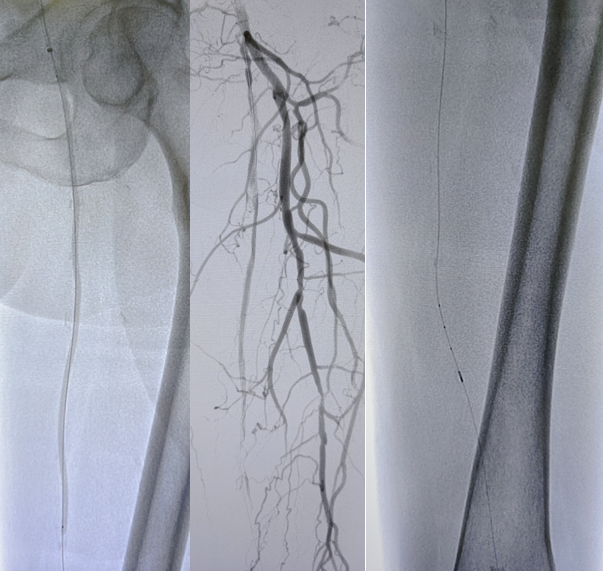

病例2(股腘动脉长段闭塞):

另一例长段闭塞病变,IVUS证实导丝真腔通过后,指导术者选择了合适尺寸的Rotarex导管进行减容,联合普通球囊(POBA)预扩及DCB治疗,获得了满意的管腔,避免了支架植入。

图:导丝通过后3mm球囊预扩

图:多处假腔通过,遂5mm球囊预扩